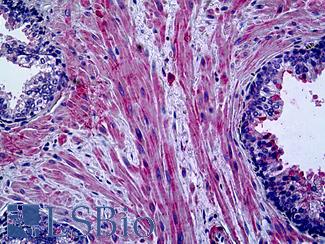

Smooth Muscle Actin (SMA / ACTA2)

Anti-Smooth Muscle Actin antibody IHC of human prostate, smooth muscle. Immunohistochemistry of formalin-fixed, paraffin-embedded tissue after heat-induced antigen retrieval. Antibody LS-B7351 dilution 1:50.